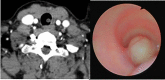

We report a case of primary tracheal schwannoma in a 31-year-old woman. She had a previous history of follicular thyroid carcinoma treated surgically and Turner syndrome. In a follow-up computed tomography scan, we found a partially obstructing intraluminal tracheal tumor, which was confirmed by bronchoscopy. The patient was treated by surgical resection and primary tracheal anastomosis. The tumor was 14 mm in diameter, with an intact capsule. Histologic analysis revealed a Schwann cell origin tumor.